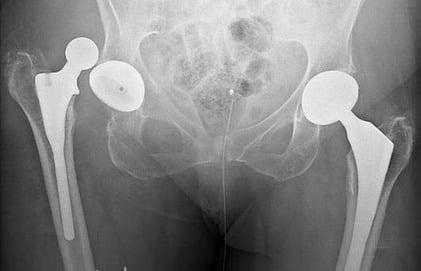

Боли и осложнения после эндопротезирования тазобедренного сустава

Как показывают исследования, осложнения после эндопротезирования тазобедренного сустава развиваются у 1 % молодых людей и у 2,5 % пожилых пациентов. Несмотря на мизерную вероятность развития негативных последствий, они могут коснуться любого, а особенно тех, кто не соблюдал в строгости программу реабилитации.

Изображение положения эндопротеза в теле человека.

К осложнениям после эндопротезирования тазобедренных суставов приводят неправильный постоперационный уход и режим физической активности после выписки из стационара. Вторая причина это ошибки врача-хирурга. И третья, это неполноценное предоперационное обследование, в результате которого не были вылечены скрытые инфекции(гланды, цистит и т.д.) На успех лечения влияет квалификация медперсонала, где пациент получал высокотехнологичную медицинскую помощь - хирургическое и реабилитационное лечение.